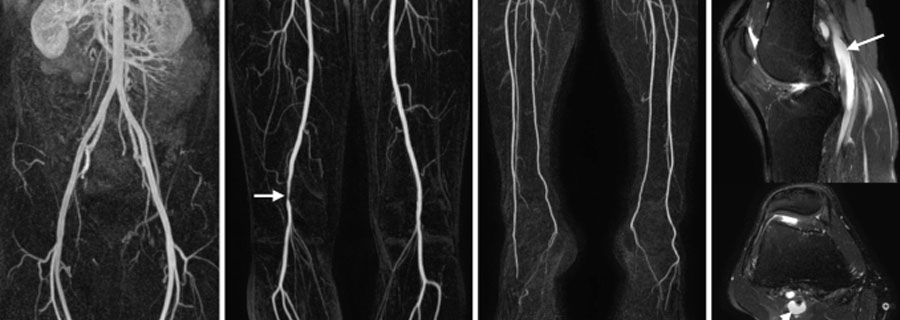

Noninvasive angiography of peripheral arteries is a medical imaging technique used to visualize and assess the blood vessels in the peripheral parts of the body, such as the arms, legs, and neck, without the need for invasive procedures like catheterization. It is primarily employed to diagnose conditions related to peripheral arterial disease (PAD) and evaluate blood flow in these areas.

Several noninvasive imaging modalities can be utilized for peripheral angiography:

• Duplex Ultrasonography: This technique combines conventional ultrasound imaging with Doppler ultrasound to visualize blood flow and identify any abnormalities in the peripheral arteries. It can measure blood flow velocity and detect areas of stenosis or blockage.

• Magnetic Resonance Angiography (MRA): MRA uses a magnetic field and radio waves to create detailed images of blood vessels. It is particularly useful for visualizing larger vessels and is less reliant on contrast agents than computed tomography (CT) angiography.

• Computed Tomography Angiography (CTA): CTA involves the injection of a contrast dye into a vein to enhance the visibility of blood vessels while performing a CT scan. It provides high-resolution images of peripheral arteries and can identify arterial stenosis or occlusions.